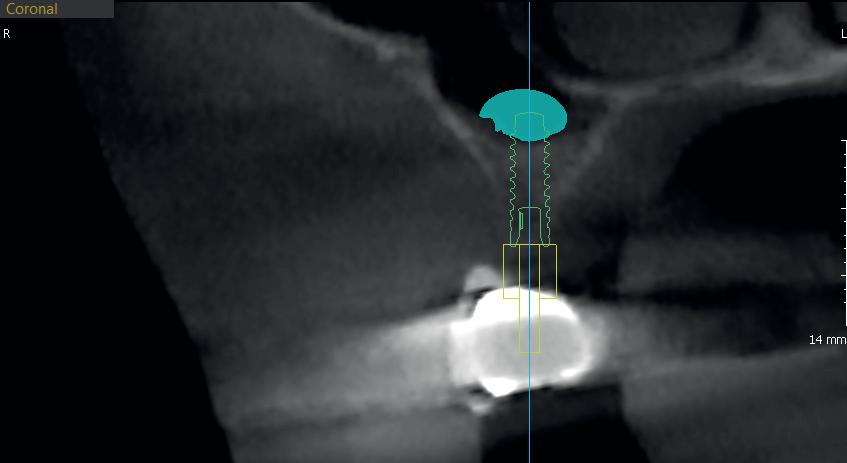

Mide, elige marcas incluyendo coloca el

Eficiencia y precisión

Eficiencia y precisión en implantología

Evalúa la densidad ósea e inserta

el implante

el implante en sólo 3 clics.

estructura

Examina la estructura anatómica de acuerdo a la hipo o hiperdesnisas que presente la zona a estudiar.

Mide el volúmen en mm cúbicos.

elige el tipo de implante (tenemos +60 incluyendo las más importantes) y el implante.

¡EN SÓLO 3 CLICS!